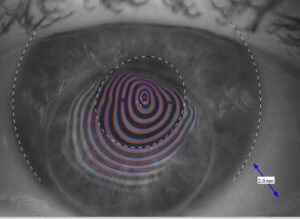

Anpassung einer Sklerallinse nach einer Hornhauttransplantation

Hier ist eine sehr starke unregelmäßige Hornhautverkrümmung des Hornhaut-Transplantates sichtbar. Die farbigen Ringe zeigen die straken Krümmungsunterschiede der Spenderhornhaut. Die Sehachse ist am oberen Rand des eingenähten Hornhaut-Transplantates. Eine Hornhautstufe ist deutlich erkennbar am oberen Rand des Transplantates. Dadurch war die Sehleistung mit 5% sehr eingeschränkt. Mit der Sklerallinse konnte der Kunde eine Sehleistung von über 80% erreichen, da diese Linse die Unregelmäßigkeiten deutlich ausgleicht und das Licht wieder auf eine gleichmäßige Oberfläche am Auge trifft.